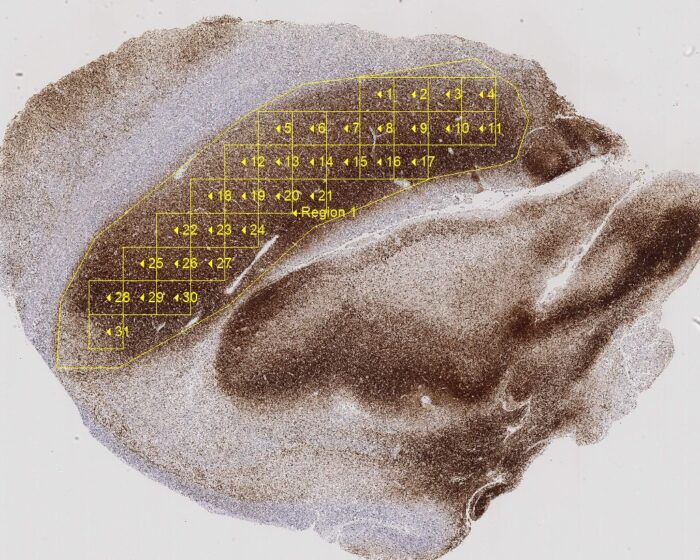

- Histology/Pathology

- Biomedical

- Life Science